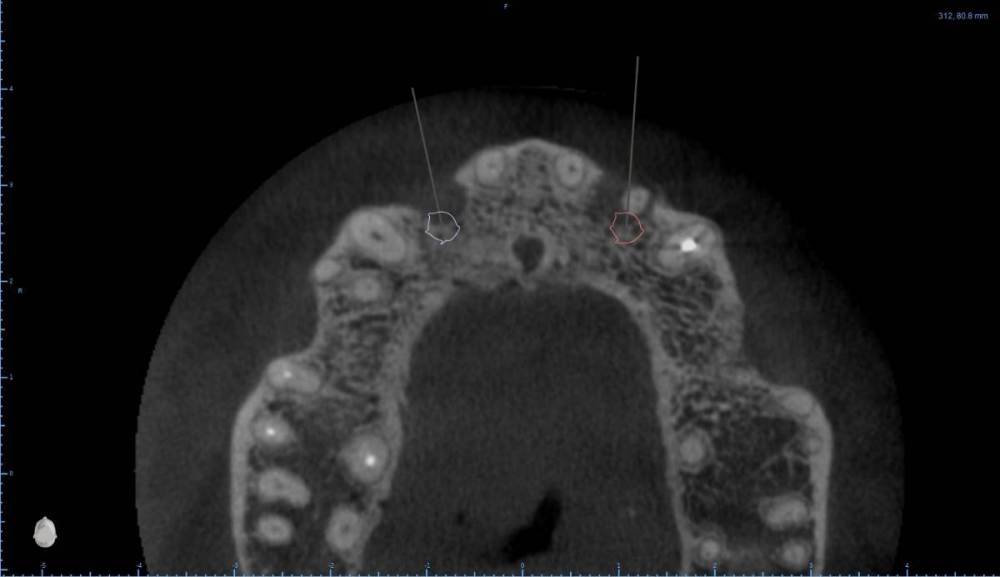

Женька Опубликовано 6 августа, 2022 Поделиться Опубликовано 6 августа, 2022 В общем планируется большая (по крайней мере для меня) работа. Вот такой товарищ у нас. Делали бы НКР в области 2.5з? или поставили бы чисто по кости, а оголённый участок закрыли присыпкой и мембраной? Также вопросы по двойкам имеются. Бугор есть, сразу оговорюсь, правда только с одной стороны. Также не понятно пока "как его правильно готовить" этот бугор, чтобы закрыть такие дефекты вестибулярной пластинки. Скрины постарался нарезать по максимуму. Там ещё будет ортодонтия конечно же. Интрузии, движения всякие и тд) Да, знаю, что планировать без цифрового гипса неправильно, но что имею. Ссылка на комментарий

Irouil Опубликовано 6 августа, 2022 Поделиться Опубликовано 6 августа, 2022 Если будет ортодонтия, то не проще ли вытянуть двойки чтобы вырастить ткани? ИДР тут нужен основательный очень, винты придётся крутить тоже очень длинные В области премоляра не вижу смысла что-то графтить, если хочется чего-то натолкать - можно стружки со сверла упаковать в дефект, но имхо не обязательно. А если сместить винт небно и чуть аннулировать, преп только пилотным и дальше конденсировать... ну Вы поняли 1 Ссылка на комментарий

Женька Опубликовано 6 августа, 2022 Автор Поделиться Опубликовано 6 августа, 2022 (изменено) @Irouil ортопед вряд ли согласится на такое. Может тогда проще пойти отсроченно? Удалить, кюретаж, губку в лунки и мэриленд (каппа с зубами) на 3 месяца. А потом уже выдумывать пластики по факту новой КТ? Винты 14мм максимум что есть По премоляру вот тоже думаю, что игра не стоит свеч. А двойки... признаться я уже ортопеду сказал, что отсрочено пойдём... хотя конечно пока всё ещё раздумываю Изменено 6 августа, 2022 пользователем Женька Ссылка на комментарий